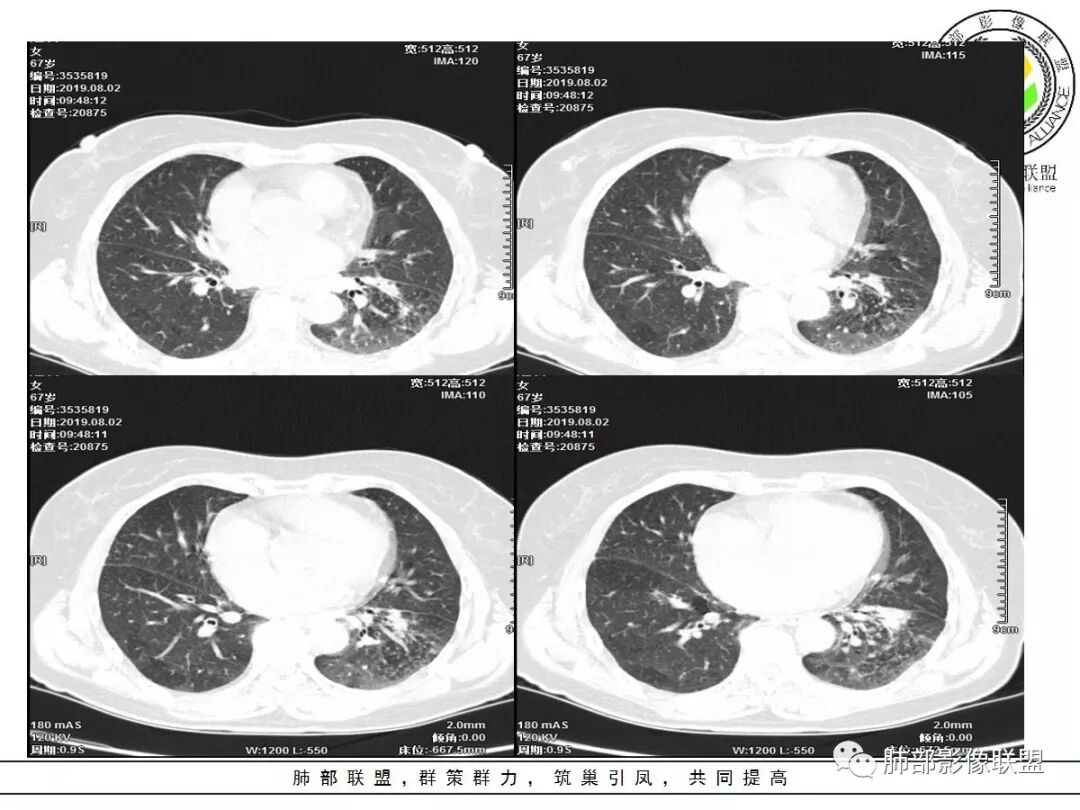

1.老年女性,咳嗽气短2月余,伴发热。病程较长,抗炎疗效不佳。

2.左肺下叶片状影及多数有边界的结节影,较散,多形性,密度不均(注意许多老师提到这个特点还是比较明显的)。左肺下叶体积未见缩小。

4.左下叶支气管壁增厚,管腔不均匀狭窄,没有堵塞

5.肺门纵隔见增大钙化淋巴结。提示曾经存在慢性病损可能。

1.前述特点除强化外都还是很容易让人首先想到肺结核的可能性。结核是常见病。注意肉芽肿明显的结核灶可以观察到强化。